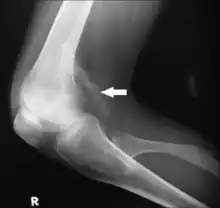

Typically, the diagnosis of extra-skeletal ectopic calcification is quite straightforward. A physical examination of a suspected area with calcified deposits palpates as hard and rough. To confirm, the calcified tissues can be seen on an x-ray.